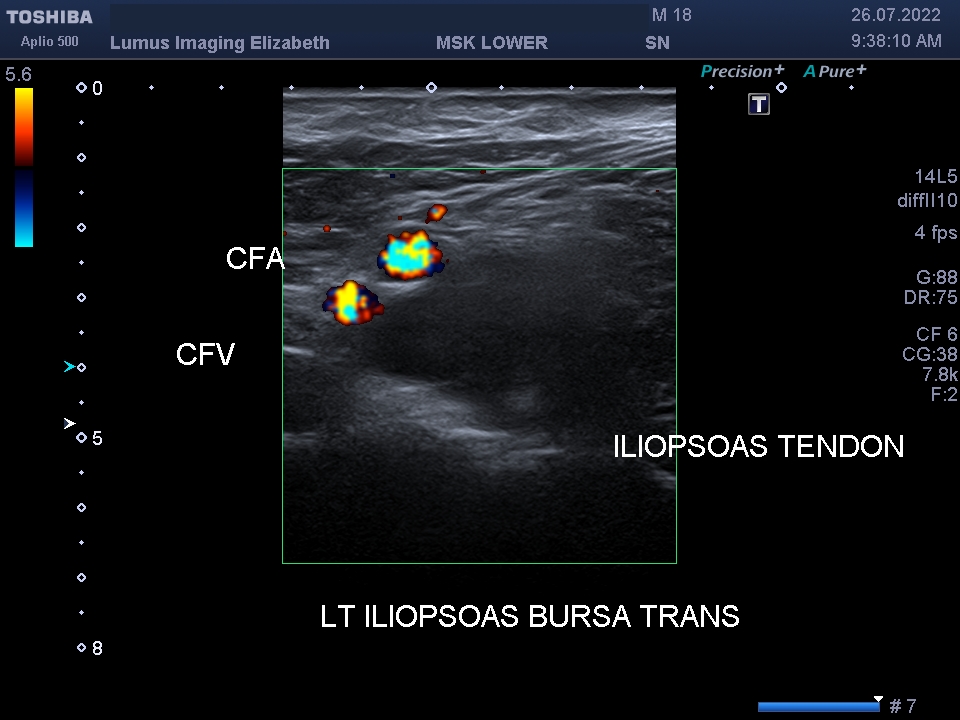

I202207261120141360017

Son Nguyen

26/07/2022